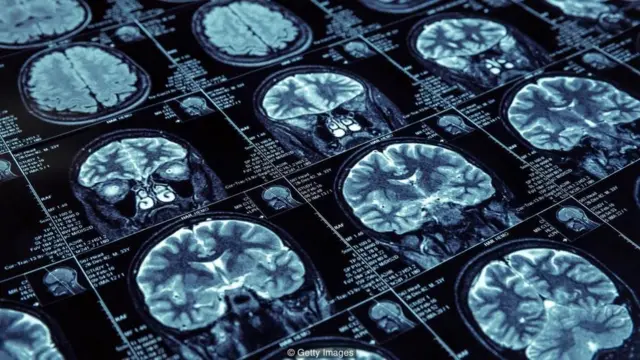

પથારીની ઉપર એક નાનું ઇલેક્ટ્રૉએન્સેફેલૉગ્રાફી (ઈઈજી) મશીન છે. પ્રયોગમાં ભાગ લેનારાનાં લોકોનાં માથા પર ઇલેક્ટ્રૉડ્સ લગાવાયા હોય છે, તેનાથી મગજમાં ચાલતી ગતિવિધિને નોંધવાનું કામ આ મશીનમાં થાય છે.

મગજના જુદા જુદા ભાગોમાં (ફ્રન્ટલ, ટેમ્પોરલ અને પેરિએટલમાં) થતી હલચલ નોંધવા ઉપરાંત હડપચી પર લગાડેલા ઇલેક્ટ્રૉડથી સ્નાયુઓની હલચલ તથા (બંને આંખની બાજુમાં લગાવેલા ઇલેક્ટ્રૉડથી) આંખની હલચલ પણ નોંધવામાં આવે છે.

પરસાળમાં થોડે આગળ કન્ટ્રોલ રૂમ બનાવેલો છે, જ્યાં બેસીને સંશોધકો રિયલ ટાઇમમાં દરેકના મગજમાં થતી ગતિવિધિને નિહાળી શકે છે.

મગજનો કયો હિસ્સો સક્રિય થયો, કેટલો સમય અને કેટલી તીવ્રતા સાથે તેને મોનિટર કરી શકાય છે.